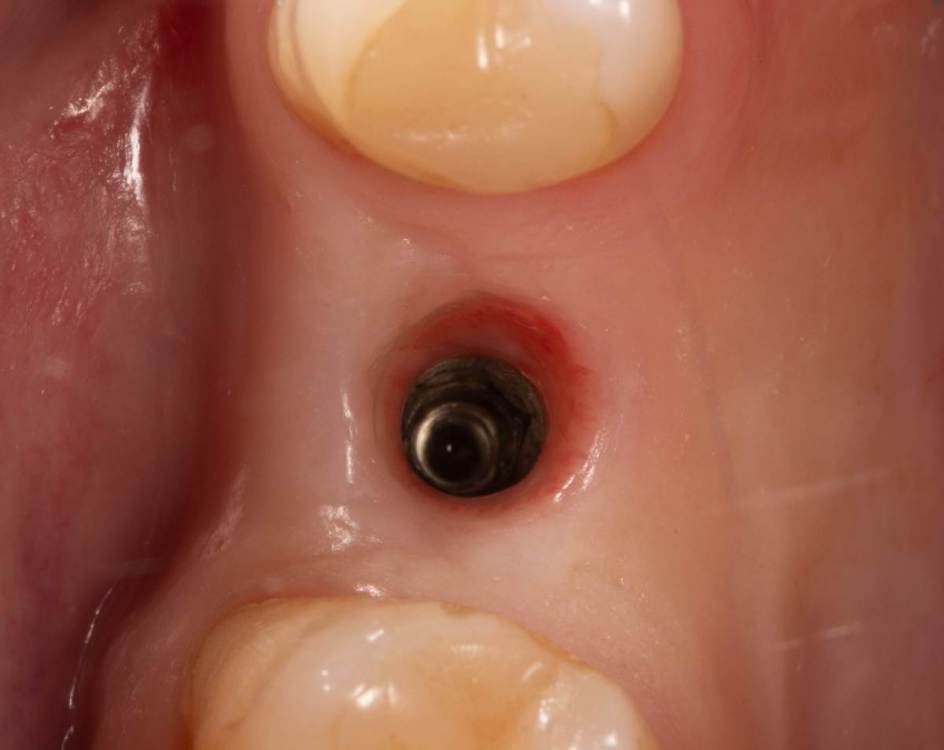

Женька Опубликовано 10 мая, 2022 Автор Поделиться Опубликовано 10 мая, 2022 Раскрылся тут недавно. Контур естественно вогнутый был, не сработал мой сст (а если быть честным, то пожалуй умер). Снова решил попробовать ролл. Это сносный результат для этой техники? или есть "серьёзные" вопросы к её исполнению? 1 Ссылка на комментарий

Женька Опубликовано 2 июня, 2022 Автор Поделиться Опубликовано 2 июня, 2022 @annda пожалуй ролл то сработал) 4 Ссылка на комментарий

Irouil Опубликовано 24 июня, 2022 Поделиться Опубликовано 24 июня, 2022 Откровенно говоря, сработал скорее ФДМ) Ссылка на комментарий